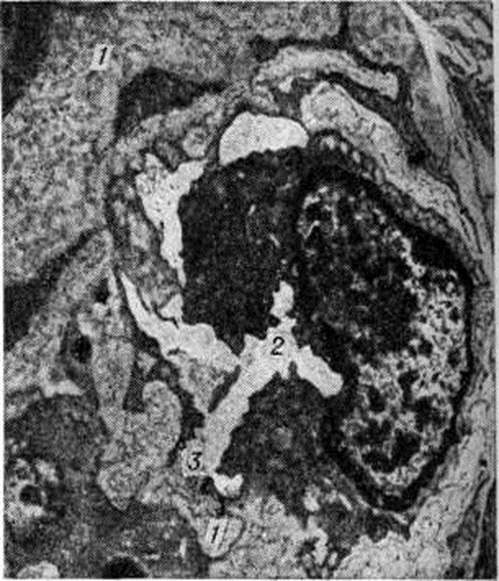

Рисунок 1.

Электронограмма гиалинизированной соединительной ткани: гиалин (фибриллярный белок) представлен в виде фибриллярных нитей; × 30 000.

Гиалиноз относится к внеклеточным (мезенхимальным) диспротеинозам. Появление в цитоплазме гиалиновых капель (гиалиново-капельная дистрофия) или шаров (гиалиновые шары) не связано с Гиалиноз. Гиалин является фибриллярным белком (рисунок 1), в построении которого принимают участие плазменные белки, в частности фибрин. При иммуно-гистохимические исследовании в гиалине обнаруживают не только фибрин, но и компоненты иммунных комплексов (иммунные глобулины, фракции комплемента). Гиалиновые массы стойки к действию кислот, щелочей, ферментов, хорошо окрашиваются кислыми красками (эозин, кислый фуксин), пикрофуксином красятся в жёлтый или красный цвет; в массах гиалина могут откладываться липиды, соли кальция. Внешний вид органов и тканей при Гиалиноз зависит от стадии процесса; чаще Гиалиноз ничем не проявляется и обнаруживается лишь при микроскопическом исследовании. В тех случаях, когда процесс выражен резко, ткани становятся бледными, плотными, полупрозрачными. Гиалиноз, в частности артериол, может привести к деформации и сморщиванию органов (например, развитие артериолосклеротического нефроцирроза, клапанного порока сердца).